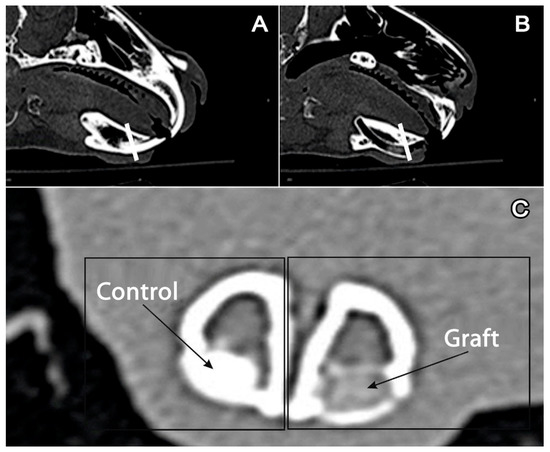

The authors studied the tissues that formed the alveolar ridge of the anterior section of the mandible. In the described anatomic area in the mandible of a rabbit, single-rooted teeth (incisors) are located. This anatomic area is shown in multilayer computed tomography (CT) images (Figure 1a–c).

Figure 1. Multilayer computed tomography of the mandible: (A) intact side, a white line goes through the incisor. (B) The side with a removed incisor and graft in the alveolar fossa, a white line goes through the graft. (C) Cross-section of the mandible. Left: preserved incisor (control); right (graft): graft in the alveolar fossa.